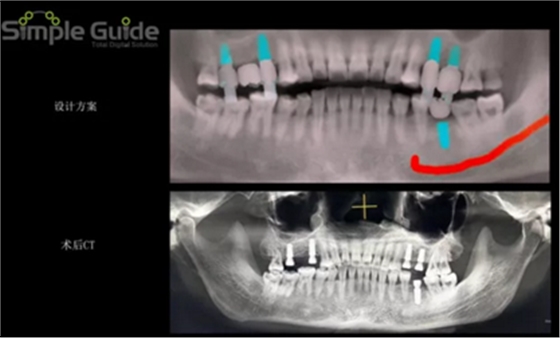

種植規(guī)劃與術(shù)后CBCT影像對比

設(shè)計植入5顆種植體

繪制下頜神經(jīng)管

植體植入設(shè)計